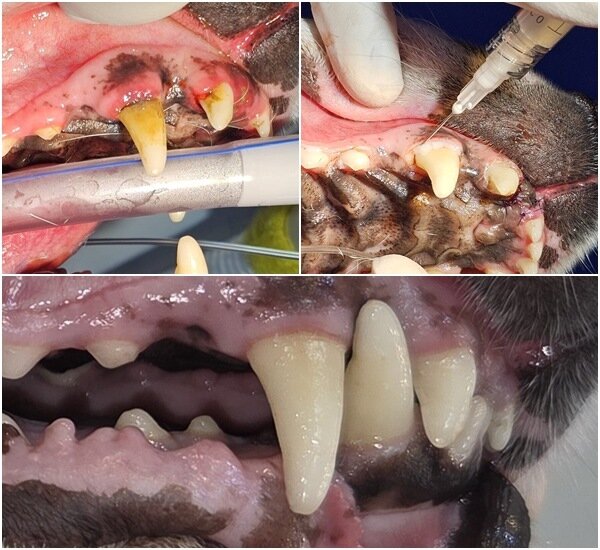

본문 이미지 - 송곳니 부위 치주염이 심해(상단 왼쪽) 스케일링 시 애니씰 덴탈콜라겐을 도포하는 모습(상단 오른쪽)과 치료 후 회복된 모습(아래) (병원 제공) ⓒ 뉴스1

송곳니 부위 치주염이 심해(상단 왼쪽) 스케일링 시 애니씰 덴탈콜라겐을 도포하는 모습(상단 오른쪽)과 치료 후 회복된 모습(아래) (병원 제공) ⓒ 뉴스1